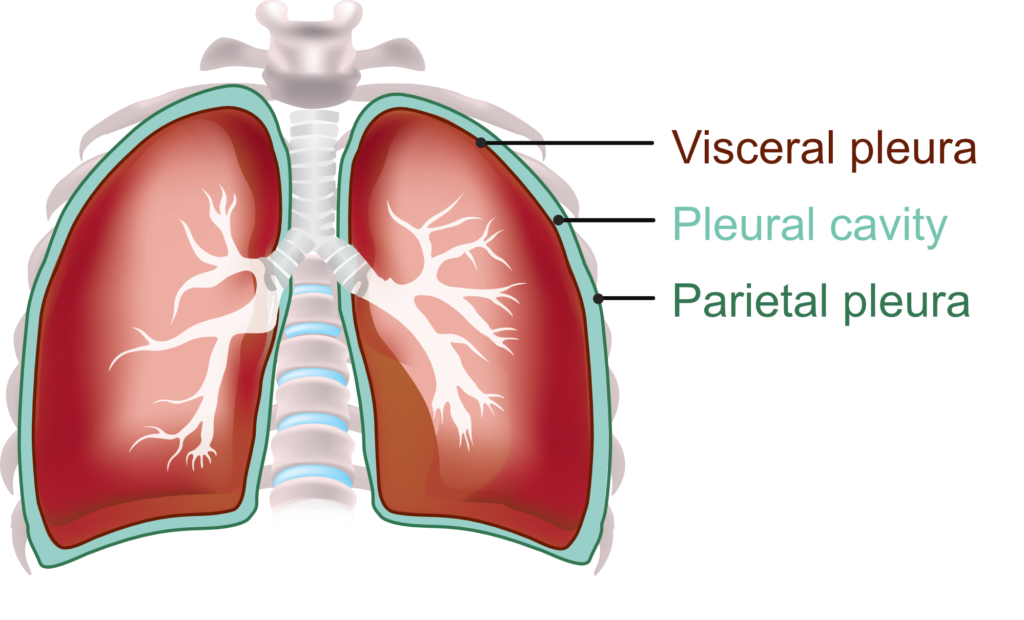

Схемы дыхания: Пневмоторакс на изображениях